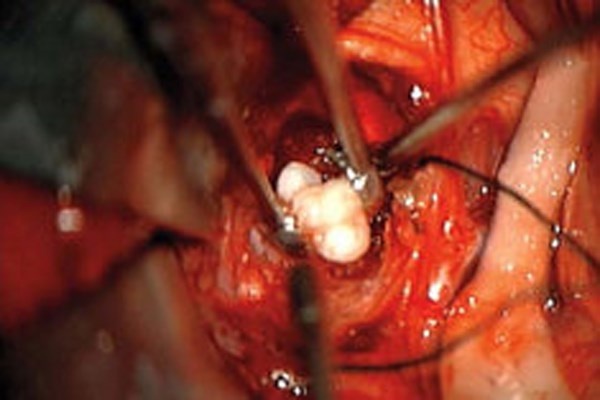

| Khối u não hình chiếc răng trong não bộ trong não em bé 4 tháng tuổi. Khối u này đã phát triển thành chiếc răng hoàn chỉnh. Sau khi phân tích các mô khối u, các bác sĩ xác định đứa trẻ có khối u craniopharyngioma hiếm gặp mà có thể phát triển lớn hơn một quả bóng golf. Được biết, em bé đang phát triển tốt. Tuy nhiên, do Craniopharyngiomas là khối u của tuyến yên - tuyến trong não chịu trách nhiệm kích thích các hóc môn quan trọng nên chúng thường gây ra các vấn đề nội tiết tố. |